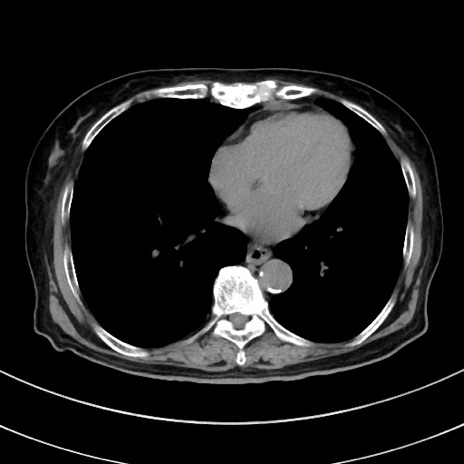

症例33(横断像)

【症例】70歳代 女性

【主訴】心窩部痛

【現病歴】延髄病変の精査・加療にて神経内科入院中。本日より心窩部痛あり。

【既往歴】虫垂炎

【身体所見】右下腹部を中心に圧痛と反跳痛あり。

【データ】WBC 10900、CRP 0.02